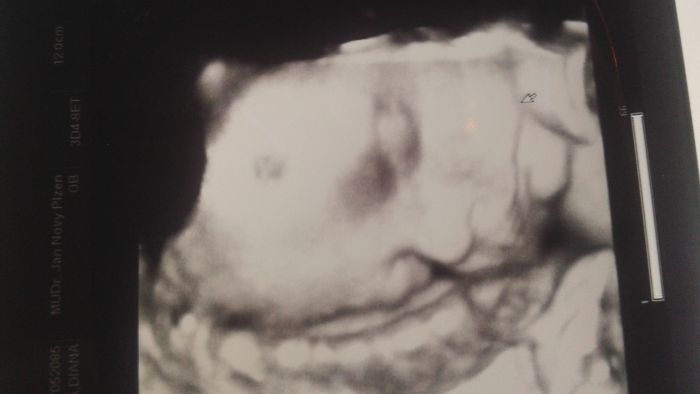

Autor: Diana 31.8.2015 v 16:16

Nevite nahodou nekdo jestli muze byt videt ve 30. tt na 3D ultrazvuku velke znaminko na cele miminka? Mam krasnou fotku z 3D ultrazvuku, ktera je krasne cista a na cela ma velky flek, ale nevypada to jako bezny stin nebo smouha. Dekuji za odpovedi:-)